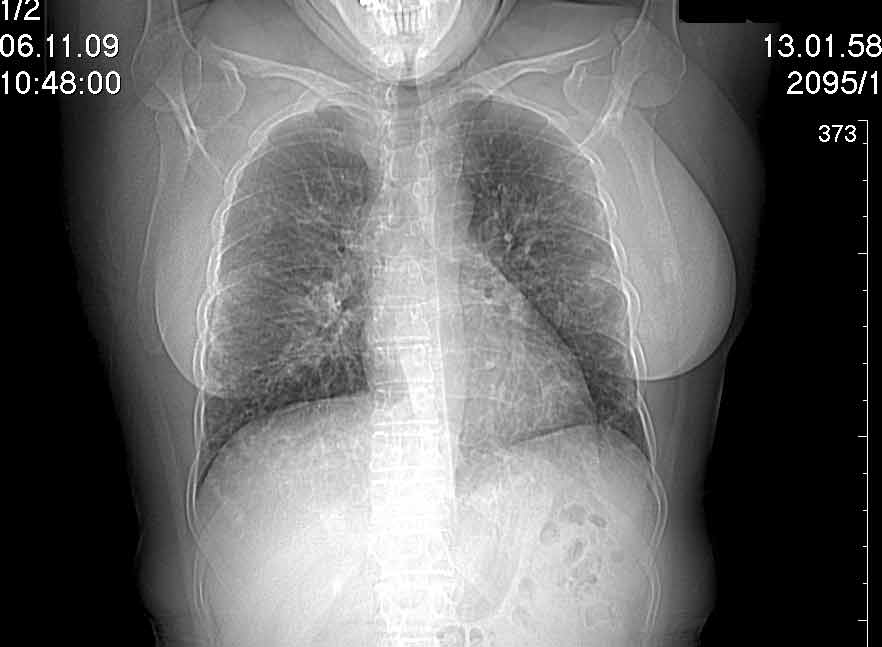

Случай №2

Мужчина 54 лет

Случай 2: картина патологических изменения довольно типична: GGOs & thickened interlobular septas = "crazy paving" sign. Наличие плотностей по типу матового стекла в сочетании с утолщением междолевых перегородок, даёт признак булыжной мостовой; на первом месте будет стоят диагноз альвеолярных протеиноз.